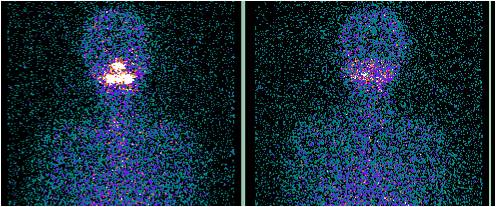

甲状腺癌颈部淋巴结及双肺转移第1次131碘治疗后显像

甲状腺癌颈部淋巴结及双肺转移第3次131碘治疗后显像(淋巴结基本清除,双肺明显好转)